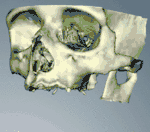

Additional procedures to augment deficient bone in implant site

Hard tissue (bone) reconstruction

Bone grafting is necessary when there is a lack of bone. Also, it helps to stabilize the implant by increasing survival of the implant and decreasing marginal bone level loss.[43] While there are always new implant types, such as short implants, and techniques to allow compromise, a general treatment goal is to have a minimum of 10 mm (0.39 in) in bone height, and 6 mm (0.24 in) in width. Alternatively, bone defects are graded from A to D (A=10+ mm of bone, B=7–9 mm, C=4–6 mm and D=0–3 mm) where an implant's likelihood of osseointegrating is related to the grade of bone.[44]: 250

To achieve an adequate width and height of bone, various bone grafting techniques have been developed. The most frequently used is called guided bone graft augmentation where a defect is filled with either natural (harvested or autograft) bone or allograft (donor bone or synthetic bone substitute), covered with a semi-permeable membrane and allowed to heal. During the healing phase, natural bone replaces the graft, forming a new bony base for the implant.[39]: 223